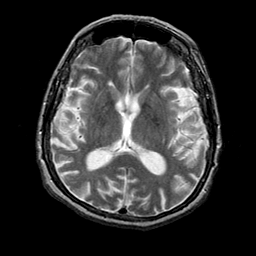

Alzheimer's disease: overlay -- Slice #13

[Home][Help][Clinical] Slice 13